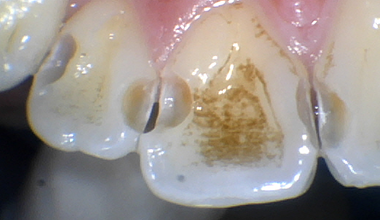

인접면 우식

충치치료 CASE

CASE 01

치료 전 -

치료 중 -

치료 후